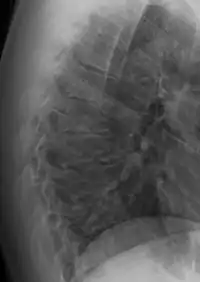

| Scheuermann's disease on lateral Xray of the T spine | |

Scheuermann's disease is a self-limiting skeletal disorder of childhood. Scheuermann's disease describes a condition where the vertebrae grow unevenly with respect to the sagittal plane; that is, the posterior angle is often greater than the anterior. This uneven growth results in the signature "wedging" shape of the vertebrae, causing kyphosis. It is named after Danish surgeon Holger Scheuermann.[3][4][5]

The seventh and tenth thoracic vertebrae are most commonly affected. It causes backache and spinal curvature. In very serious cases it may cause internal problems and spinal cord damage, but these cases are extremely rare. The curvature of the back decreases height, thus putting pressure on internal organs, wearing them out more quickly than the natural aging process; surgical procedures are almost always recommended in this case.

Diagnosis is typically by medical imaging. The degree of kyphosis can be measured by Cobb's angle and sagittal balance.